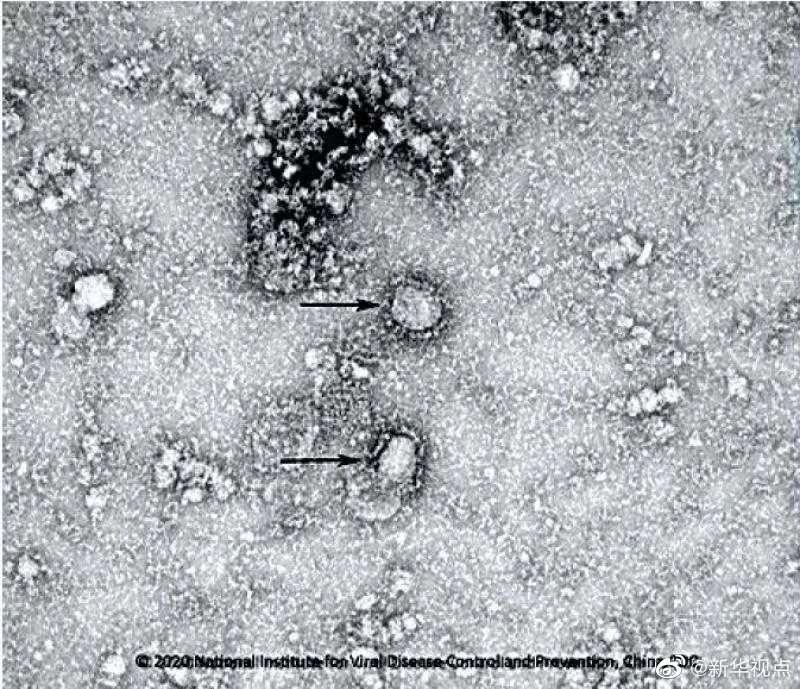

國家病原微生物資源庫于2020年1月24日發(fā)布了由中國疾病預(yù)防控制中心病毒病預(yù)防控制所成功分離的我國第一株病毒毒種信息及其電鏡照片、新型冠狀病毒核酸檢測引物和探針序列等國內(nèi)首次發(fā)布的重要權(quán)威信息,并提供共享服務(wù)??床《尽罢嫒荨薄ㄓ浾咛飼院?、王秉陽)